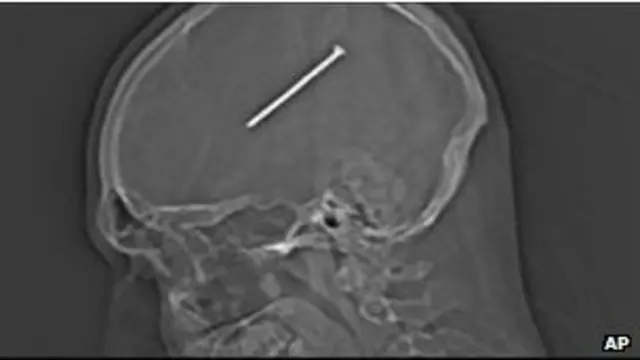

Seorang lelaki pinggir kota Chicago secara tidak sengaja menembakkan paku sepanjang 8,25cm ke dalam tengkoraknya.

Saat dokter sukses mengeluarkan paku tersebut keluar dari otaknya, terungkap bahwa paku tersebut hanya berjarak milimeter dari area otak yang mengontrol sistem pergerakan.

Tunangannya, Gail Glaenzer kepada kantor berita Associated Press Jumat kemarin mengatakan dia dalam kondisi yang bagus setelah menjalani dua jam operasi untuk mengangkat paku dari otak bagian tengah di Pusat Medis Oak Lawn, Illinois.

Autullo memperkirakan paku itu masuk ke dalam otaknya akibat sensor pistol paku yang terhentak oleh permukaan datar dan menembak.

Juru bicara rumah sakit Mike Maggio mengatakan bagian dari tengkorak yang terkena tembakan kini diganti dengan besi titanium karena khawatir telah terkontaminasi paku.